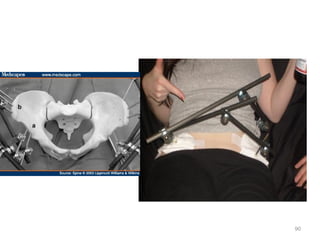

Pelvic fracture

Pelvic fracture Dx?

Source of bleeding ?

Mx?